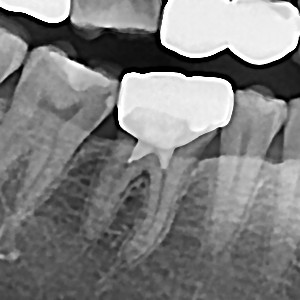

충치치료&신경치료 하루에 끝나는 신경치료

60bab75a1a70db4a6fd0ef2b4df1f9ae_1767344664_5957.jpg